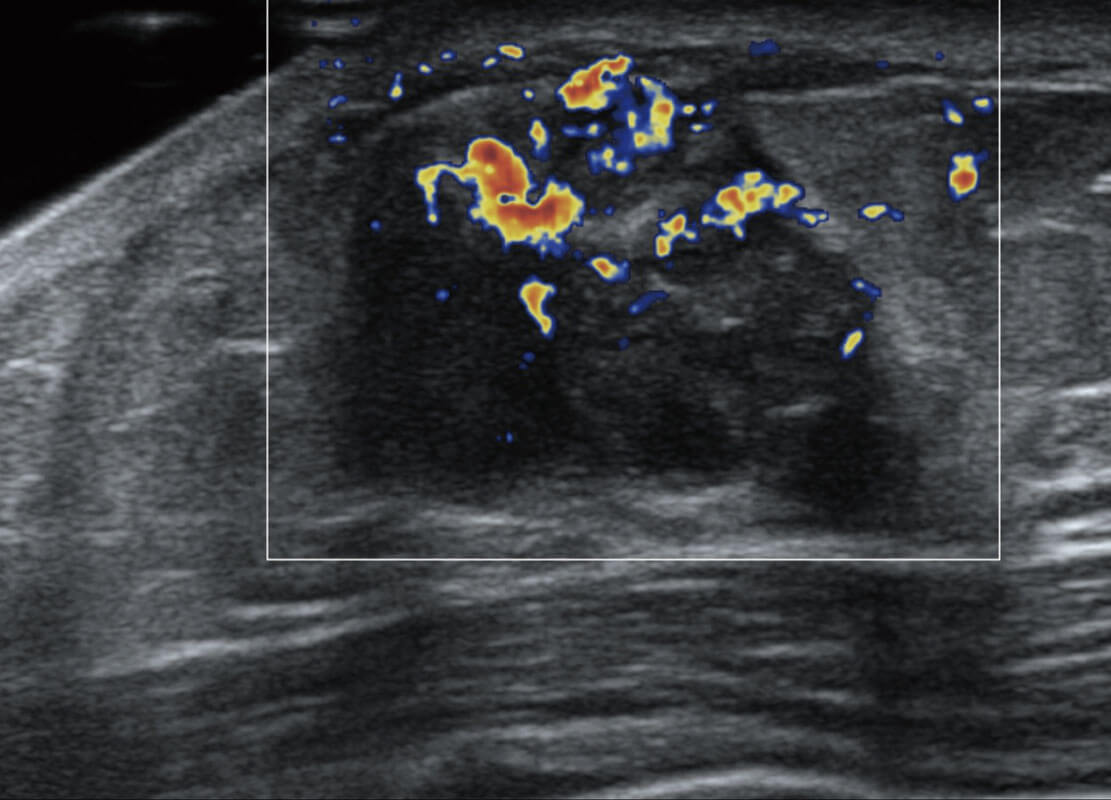

P60搭载宽频带线阵探头、宽景成像、弹性成像技术,为您提供乳腺应用方案。P60支持高频相控阵探头、线阵探头、腹部高频探头、腹部微凸探头等,丰富的探头群搭载敏感的彩色血流成像,适用于新生儿多种脏器检测要求,满足新生儿筛查需求。

乳腺导管癌

乳腺癌显微血流

新生儿肝血管癌

新生儿脊髓圆锥

新生儿心脏